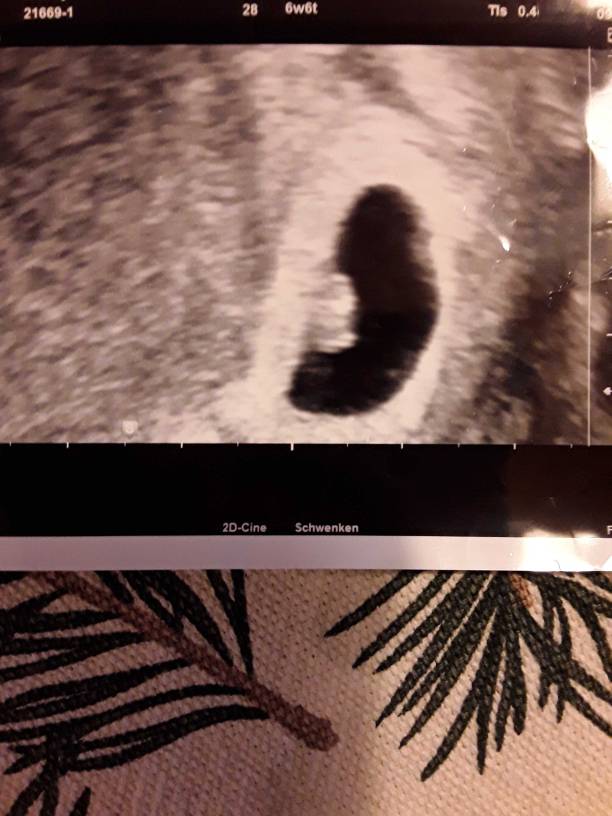

Marta ja miałam usg w 7tc ale ja nie umiem się odnaleźć na tym zdjęciu. Pokaże Ci to może coś wyczytasz. Ale życzę Ci tej córki jak sobie kiedyś [emoji173]

Patrz

1547542611208.jpeg

Wychodzi na to że chyba za po lewej na dole tak?